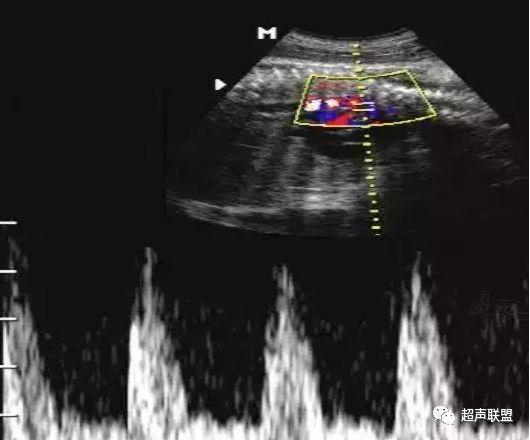

3 胎儿静脉导管

当右心负荷增大,心功能失代偿时,静脉回流受阻,静脉导管a波收缩期流速降落,血流消失甚至倒置。

5、静脉导管:a波消失或反向(见于严重的胎儿宫内缺氧);

3、静脉导管a波反向或消失;

图5 胎儿宫内正常静脉导管

图6 胎儿宫内缺氧时静脉导管a波反向